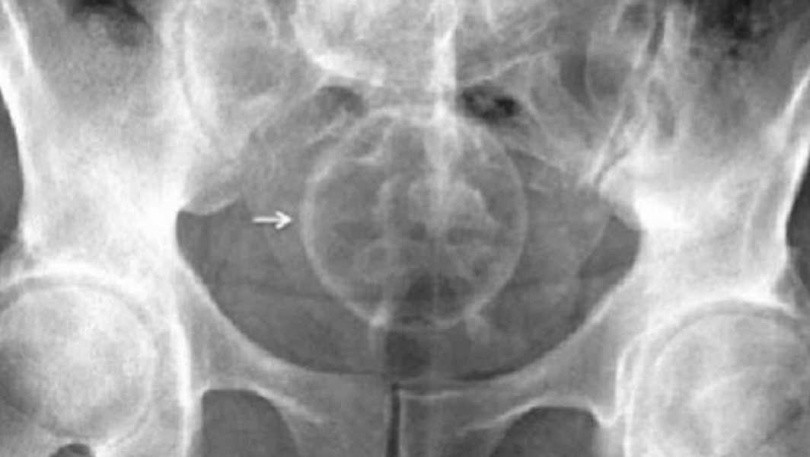

Đặc biệt, có trường hợp một cô gái trẻ sử dụng kẹo que hình gậy trang trí Giáng sinh để thử cảm giác mới. Kết quả, chiếc kẹo dính, kẹt luôn trong cơ thể. Ảnh chụp X-quang cho thấy rõ ràng một cây kẹo và một vật trang trí cây thông Noel nằm trong trực tràng của bệnh nhân.